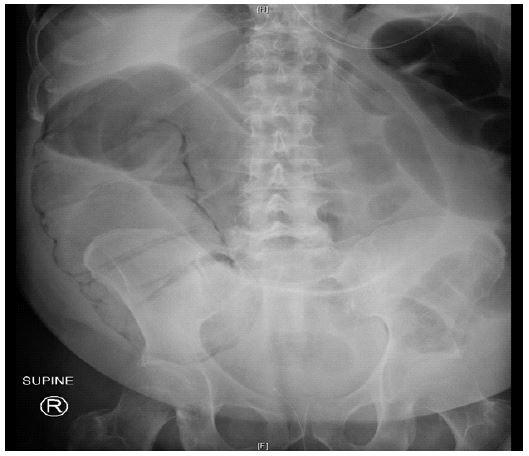

• Imaging: Chest X-ray showed hyperinflation without acute infiltrates. CT scan revealed pneumatosis coli involving the cecum and ascending colon, with no evidence of perforation or free air.

Hospital course

Figure 3: Coronal view CT abdomen and pelvis.